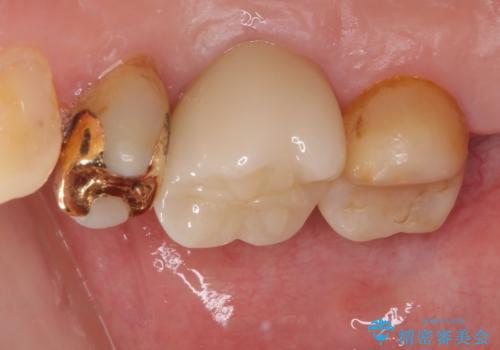

一部歯肉の中にまで虫歯が波及しており、汚れが溜まりやすくなっていましたが、クラウン装着後は汚れが溜まることはなくなりました。

しみていた症状もなくなり、患者様には大変満足していただきました。